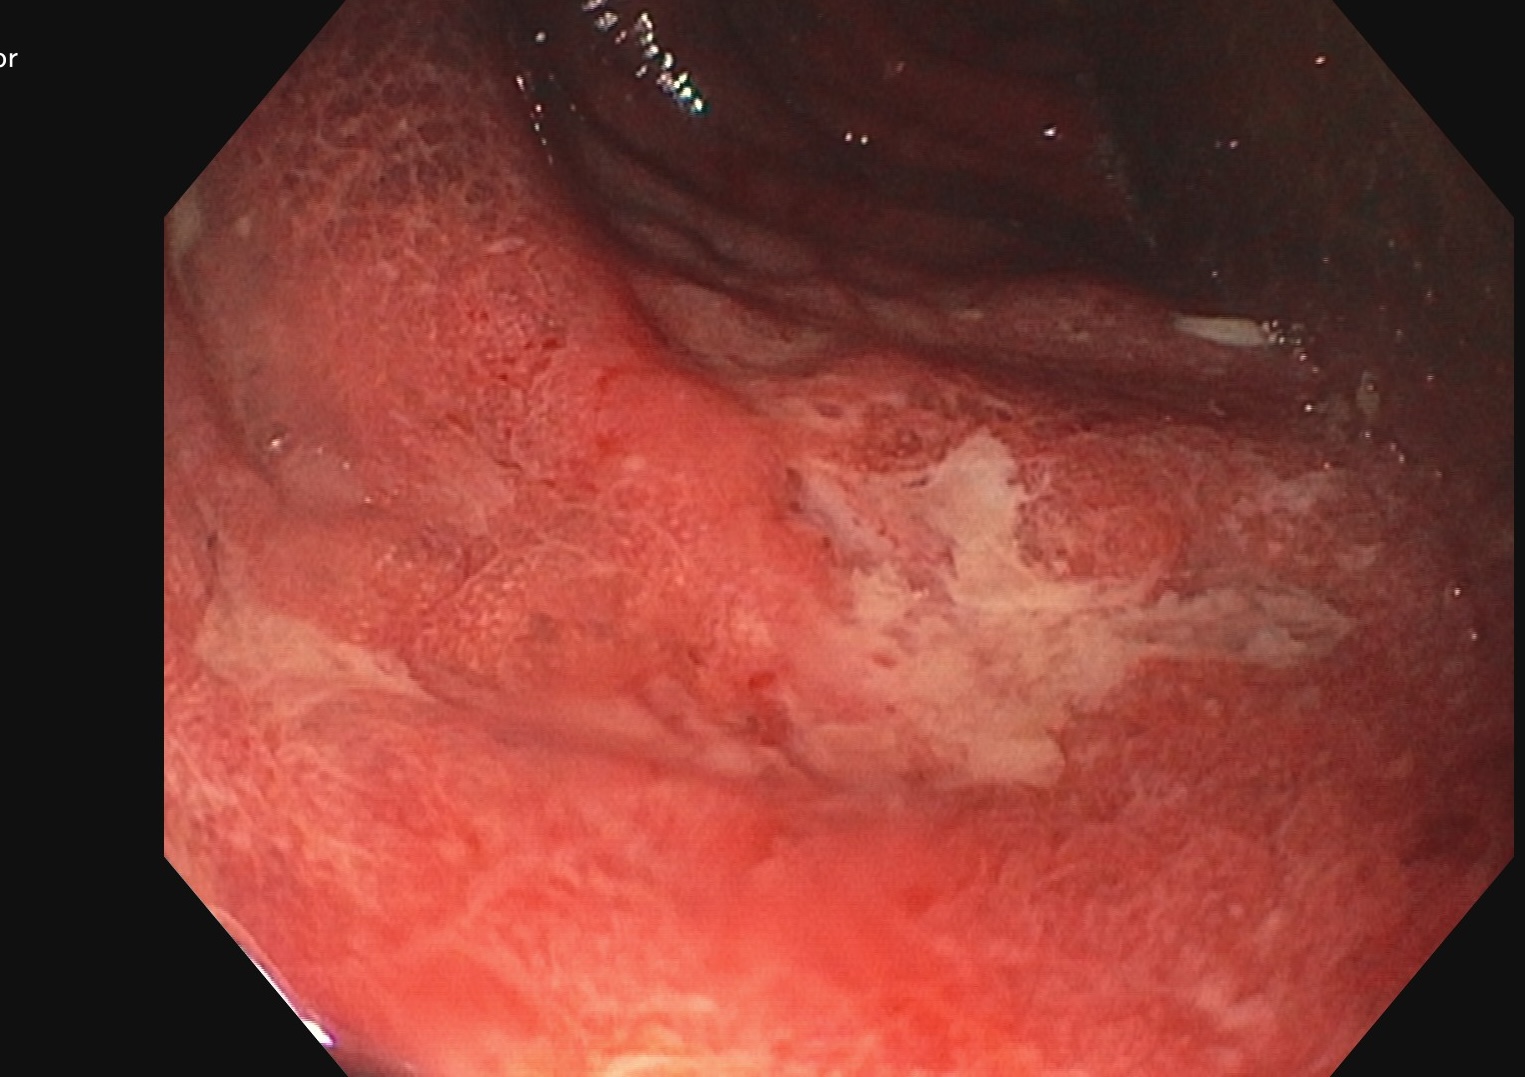

Endoscopie Mayo 3 UCESI 7/8 ulcères creusants

Les images échographiques correspondent parfaitement aux images endoscopiques, et sont finalement beaucoup plus précises que les images scanographiques.